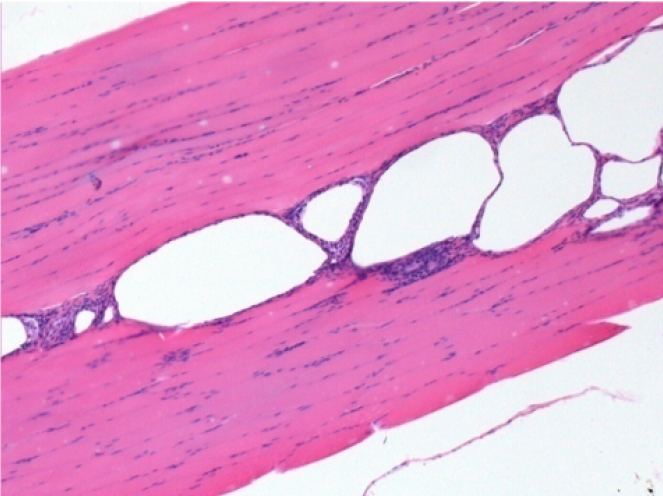

10 days after Endopeel Injection 0.1ml in the right pretibial muscle.

Here you may see the formation of the vacuoles which are surrounded by lymphocytes. Vacuoles are different from tissue necrosis . The presence of lymphocytes is related to the permeability of the cell membranes.